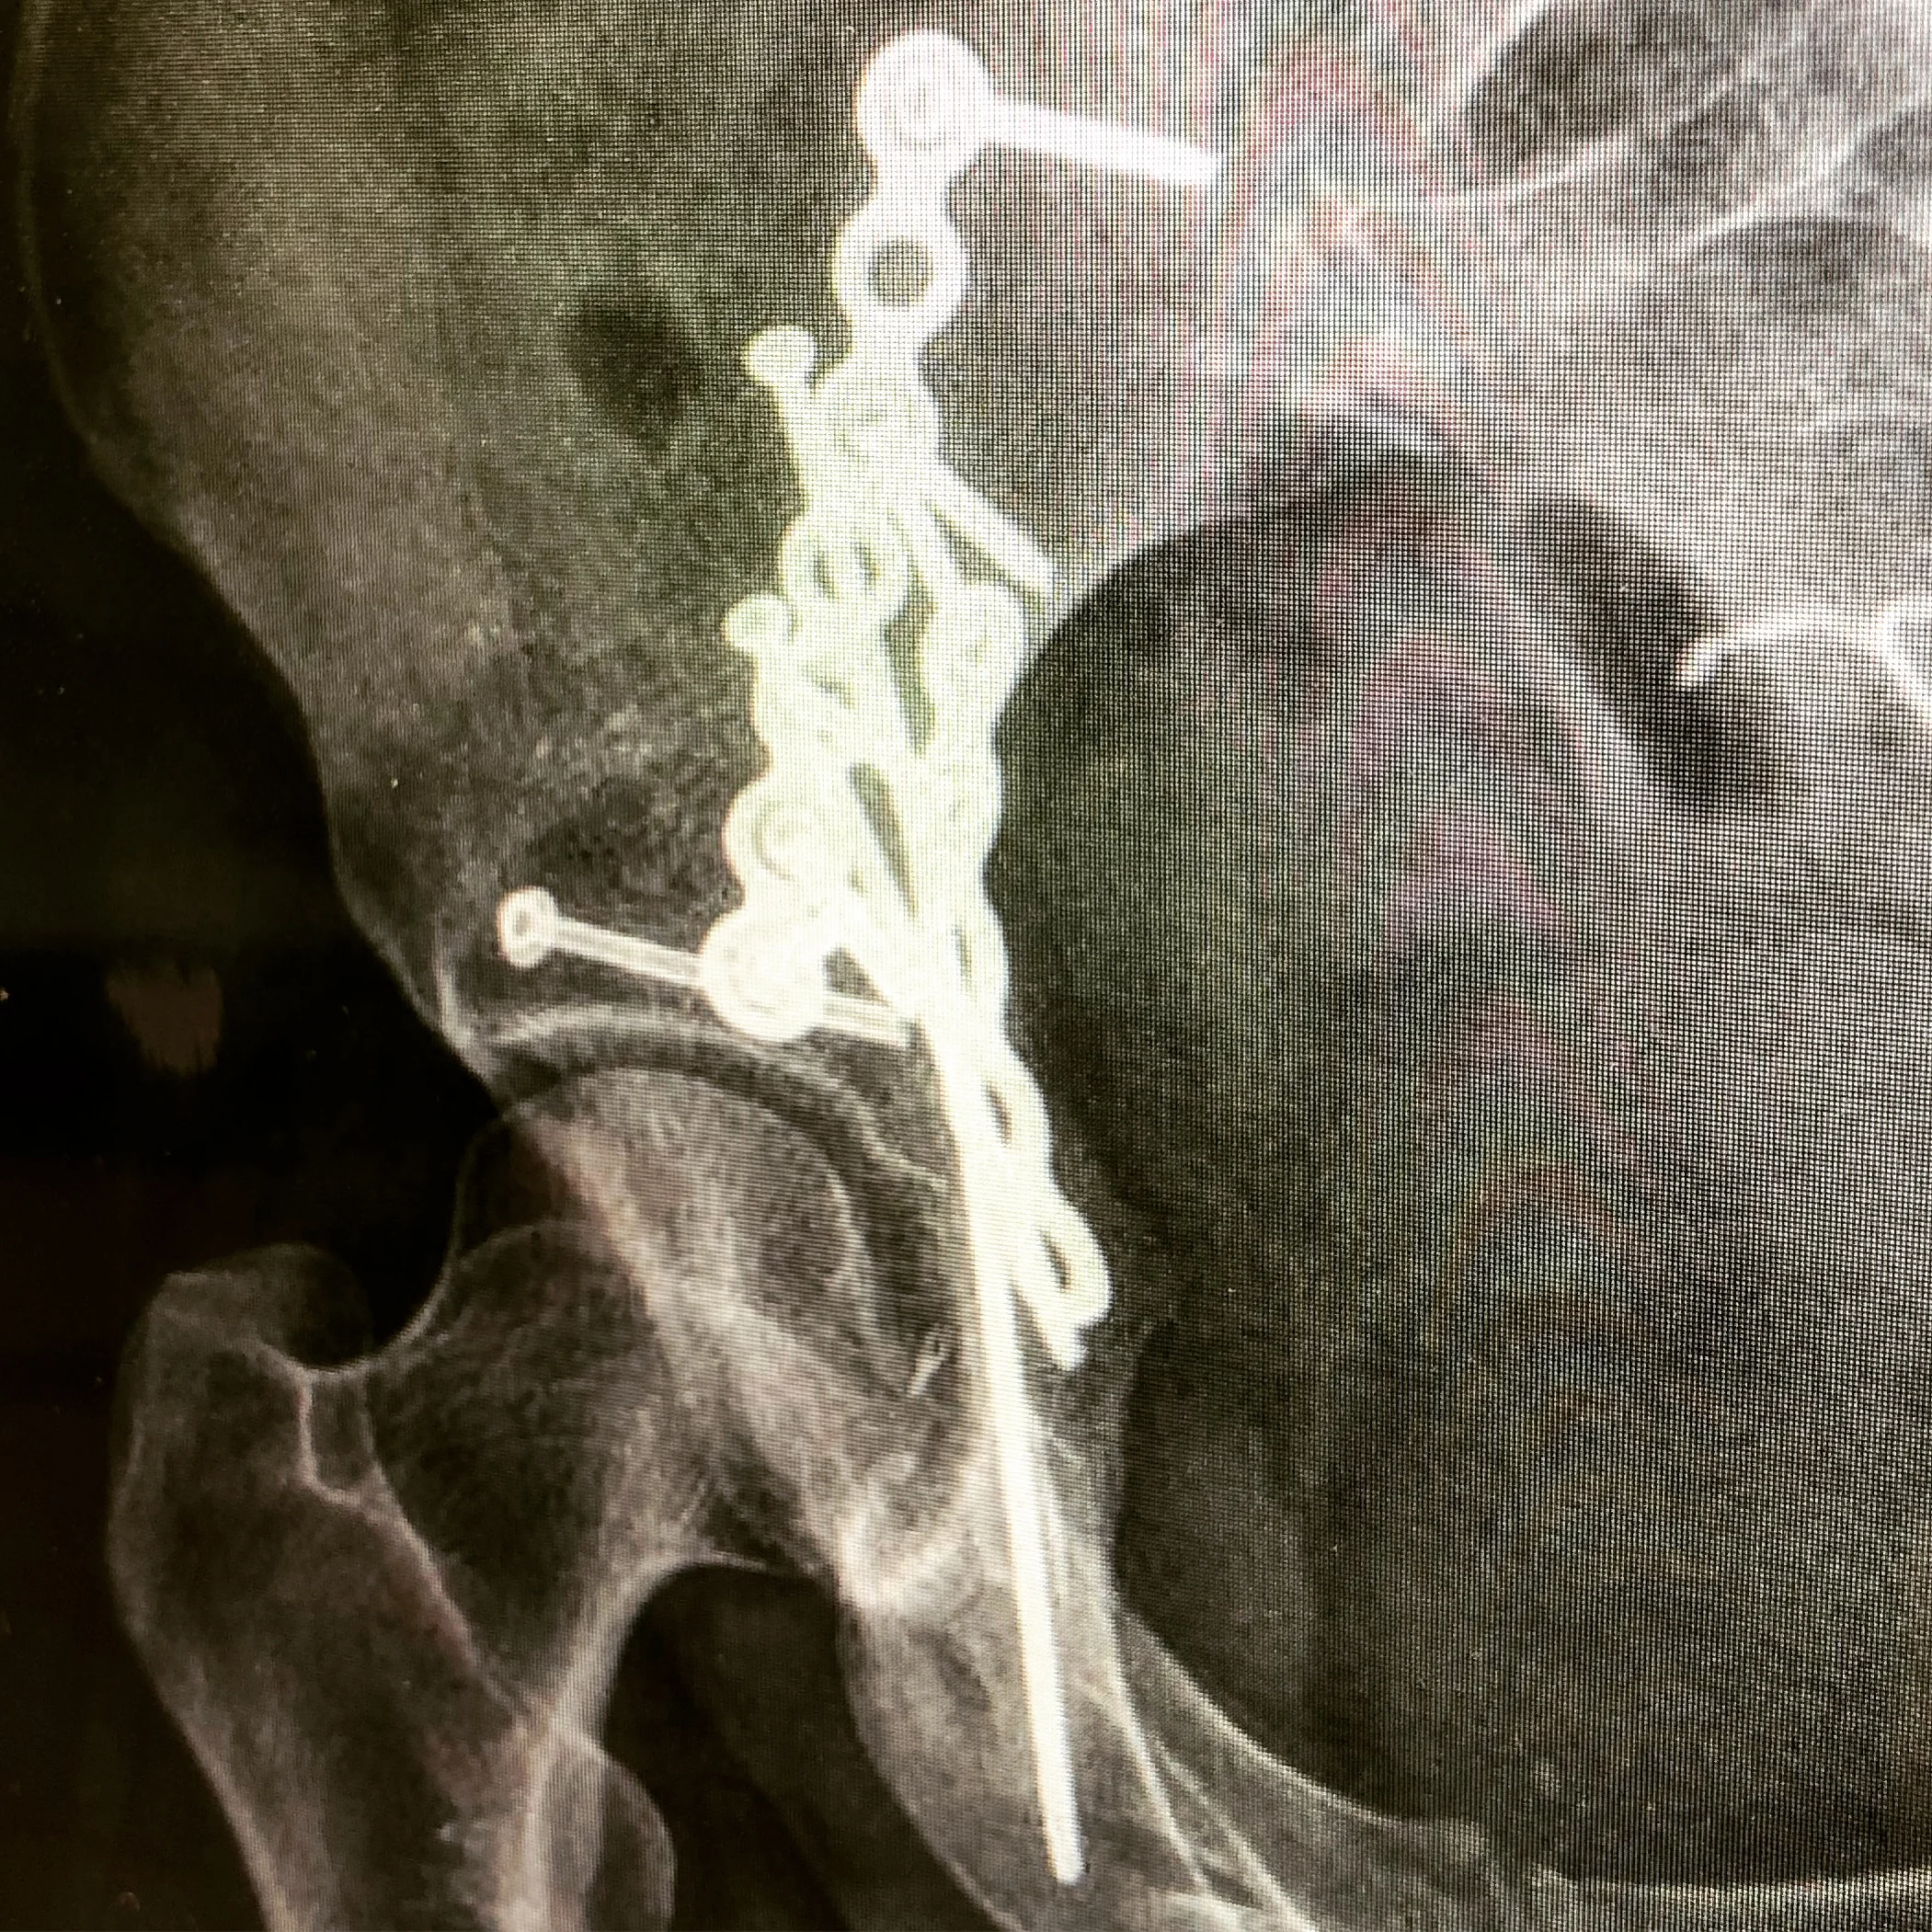

Dr. Adams greeted me after my x-rays. He reviewed the images with me and said they were exactly what he was hoping to see and they should remain unchanged for the rest of my life. The space between the ball and socket of my left hip joint is exactly equal to that of my right with no notches or rough surfaces from the bone breaks to prevent the joint from moving freely.

Updated X-Rays. Still holding strong.